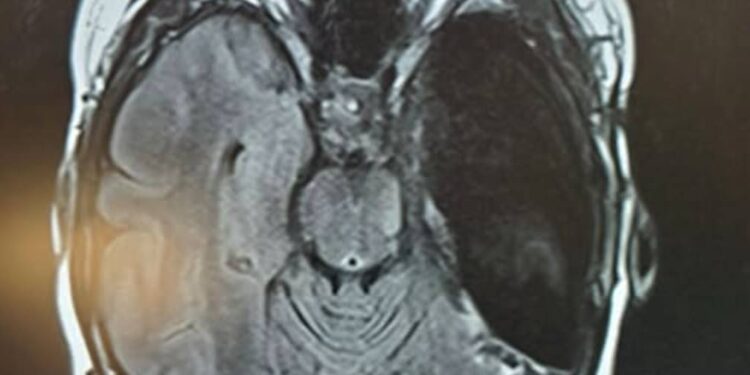

Why My Right Temporal Lobe Was Removed: Epilepsy, Mental Health, and the Road to Recovery

Right Temporal Lobectomy

At 50 I was taken to my knees by epilepsy.  I have had three invasive brain surgeries since the. 18 months ago I had my Right Temporal Lobe removed, a Lobectomy.  I am feeling much better as I recover and my brain rewires itself.  Why did I have it removed?